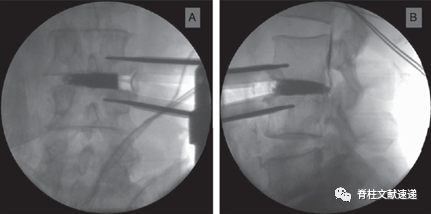

图2.术后薄层计算机断层扫描(CT)显示Cage无沉降融合(A,B)和Cage有沉降融合(C,D)。